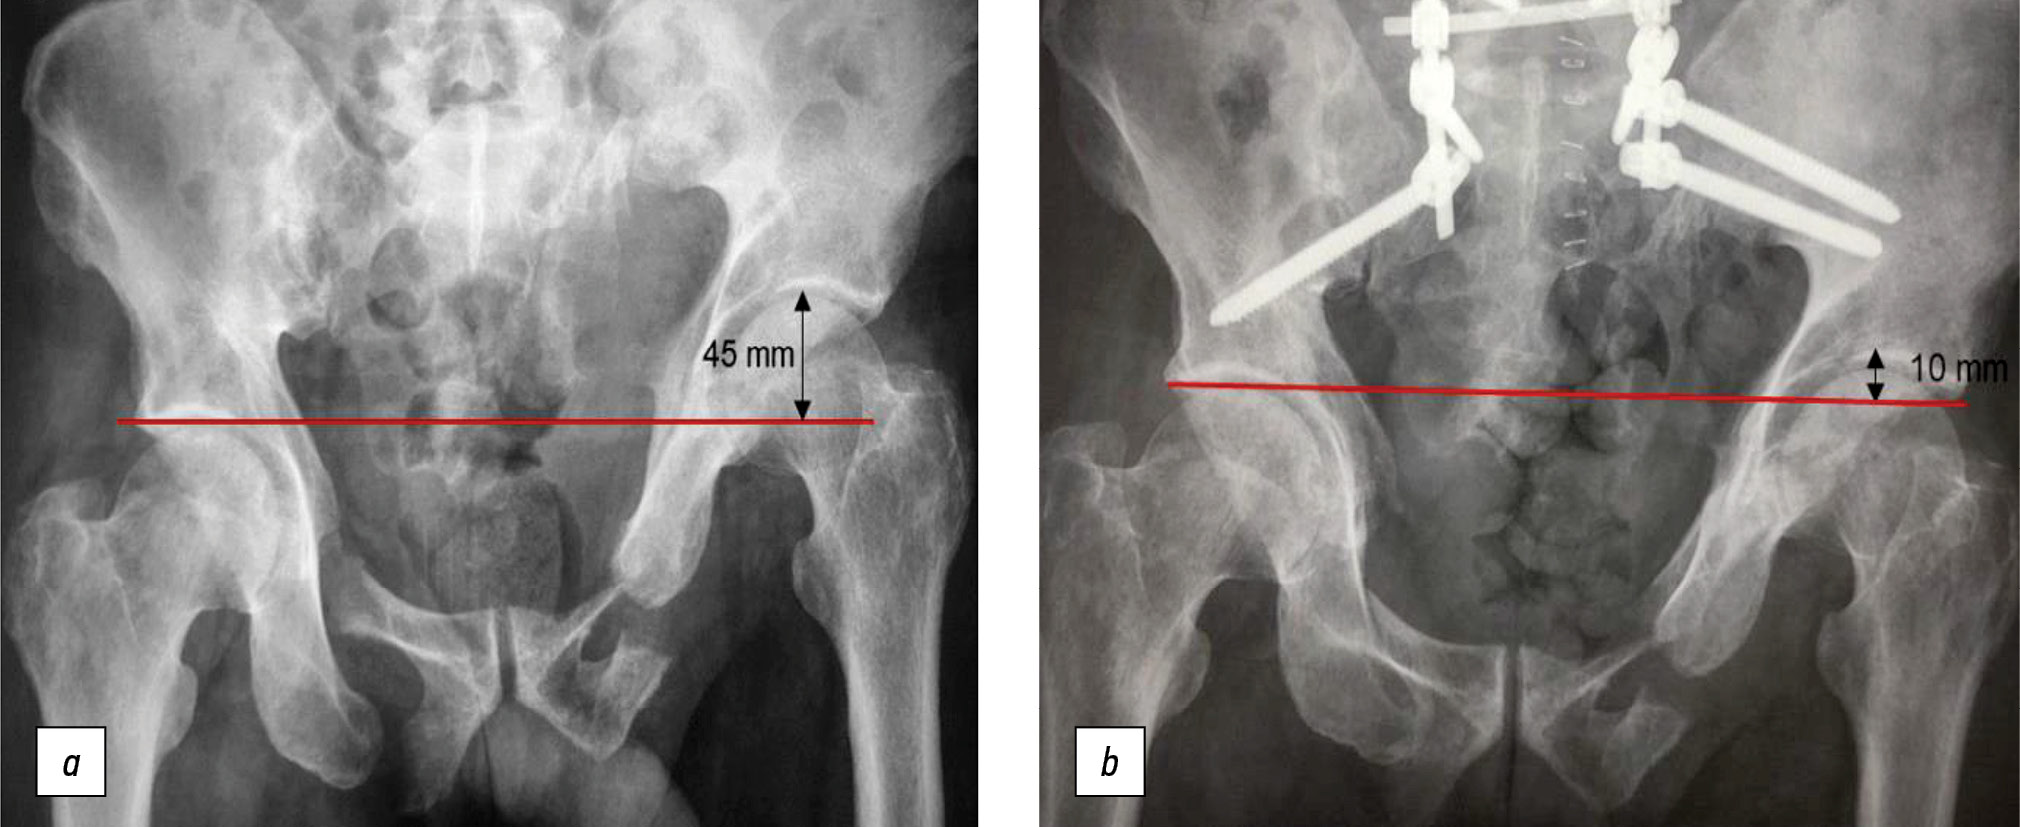

A patient aged 56 years presented 11 months after an injury (fall from the 5th floor). CT showed fractures of the pubis and ischium on both sides, and a longitudinal fracture of the lateral sacral masses on the left side in the Denis 2 area (Fig. 4).

Fig. 4. Computed tomography of the pelvic bones in 3D reconstruction mode: a — front view; b — back view.

Grade III vertical displacement according to Shlykov classification (45-mm asymmetry of the hip joints) was noted. The patient was on bed rest from the moment of injury, and no verticalization was done. Open repositioning of the left hemipelvis and bilateral PTF were performed. The surgery resulted in a 35-mm displacement and a residual displacement of 10 mm (Fig. 5).

Fig. 5. Overview radiography of the pelvis: а — before surgical treatment; b — after spino-pelvic fixation with open reposition of the left hemipelvis.